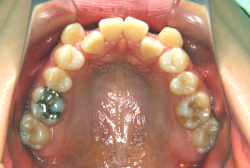

先天性欠如

先天性欠如とは生まれつき永久歯が部分的に欠如している状態をいいます。一般的に下顎前歯や小臼歯が欠如していることが多いです。

「左奥歯でものが噛めない」という主訴で来院したケースです。診断の結果、基本的には「叢生」という隙間が足りないと言うことが原因の凸凹症例でしたが、左下の乳歯が高校生になってもまだ残存している状態で、そのせいで噛み合わせが極端に悪くなっていました。

検査の結果、乳歯の下には後継ぎの永久歯が先天的に欠如していました。配列の凸凹が厳しく非抜歯で矯正することは難しく、仮に無理をして非抜歯治療をしても後々「後戻り」が懸念されることから、このような症例の場合は通常、上下顎左右第一小臼歯を抜歯させていただくのですが、左下は乳歯を抜歯して、第一小臼歯は残すことにしました。これで結果として、小臼歯部を上下左右で一つずつ減らしたのと同じ状況になります。治療後は歯並びが綺麗になっただけでなく、噛み合わせ的にも正しい状態が確立しています。

このように、先天的に永久歯が足りないという症例は最近増えています。親知らずはなくても特に問題になりませんが、その他の歯が足りないと言うのは審美的にも機能的にも重大な障害となります。しかし、矯正治療を正しく行えば、結果として歯がすべてあった場合と全く同じ仕上げにすることも可能です。